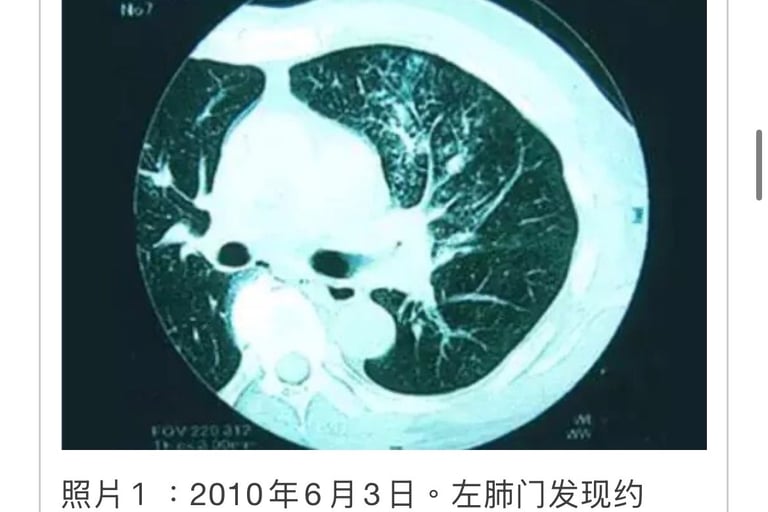

(2005.4⇒2012.11)

(肿瘤标记)T・M(1936年生、男性)2005年2月、患者打嗝不止就医未发现异常。

来我院就医,诊断发现横膈膜左侧附近有肾癌共振反应,去大医院复检结果左肾上有11×10×9cm巨大肿瘤。

05年4月4日手术摘除。术后发现左肺2个和右上叶较小转移(照片1)。

2005年4月20日来院接受MW治疗,至6月20日合计照射16次。3个转移肿瘤2个消失。2005年5月11日追加NK・T细胞免疫疗法(每隔2周共计6次)。患者恢复状态较好。3个月复检一次。

2009年1月肺癌反应出现后MW照射消失。

1月27日胸部CT成像显示左肺下叶阴影较大(照片2),患者对干扰素副作用反应明显使用终止。

对左下叶的肿瘤标记建议摘除,由于患者并无癌症共振反应所以未进行手术。12年11月至今,患者除了肌酸酐值偏高外其他指标正常。